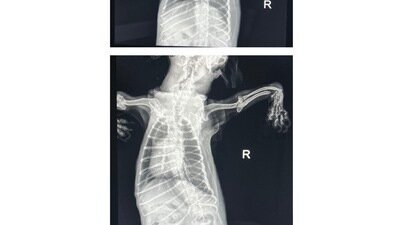

Chewy came into our clinic over a month ago with a history of being unable to move for at least 3 months. Behind those innocent eyes lay a tale of suffering. He arrived in our care bearing the scars of multiple chronic fractures, each one a testament to the neglect he endured. Our hearts broke as we witnessed his struggles during the x-rays we took, knowing the pain he was in. Yet, despite the obvious signs of distress, the City of Virginia Beach Prosecutor insists that Chewy was not in pain.

A radiologist review of his x-rays found that, “…the reported thoracic and pelvic limb abnormalities have variable chronicity and could be an indication of repeated trauma resulting in osteopenia or disuse osteopenia causing the pelvic limb fractures with subsequent subluxation. Additionally osteopenia is thought more likely to represent disuse as opposed to primary/secondary hyperparathyroidism…"

Chewy’s x-rays can be found here: https://www.canva.com/design/DAGnWK-cM94/g5-aOMit33zg9upsBcEYSQ/view?utm_content=DAGnWK-cM94&utm_campaign=designshare&utm_medium=link2&utm_source=uniquelinks&utlId=h8fa6e59574